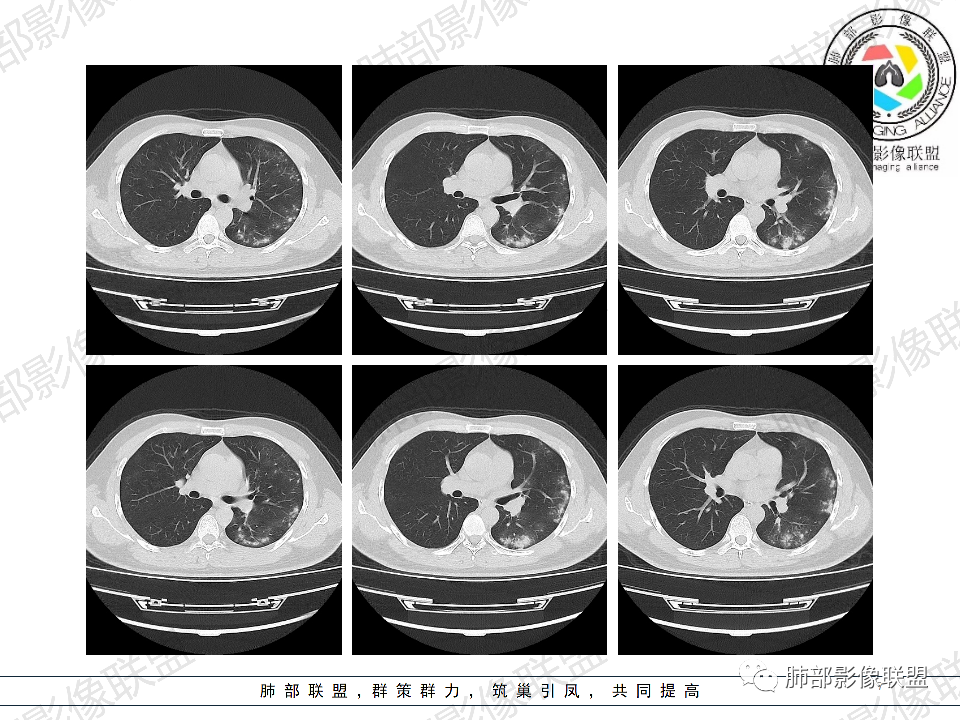

年轻男性,有HIV病史,免疫力缺陷病史,CD4明显减低,左肺胸膜下多发大小不等结节影,部分侧向融合,平行于胸膜,周围伴有模糊的GGO,部分结节与血管相连,血管束增粗,考虑隐球菌,建议查隐球菌荚膜实验,脑脊液隐球菌荚膜,鉴别:CMV(局限性比较少见)

年轻人,男性,HIV阳性,双肺多发斑片状,结节状阴影,以胸膜下分布为主,病灶与支气管血管束垂直生长,周围可见磨玻璃影,考虑肉芽肿病变,隐球菌感染可能性大,鉴别GPA,胞子菌肺炎。

双肺胸膜下多发大小不等结节伴晕征,部分似有融合

左肺多发大小不等结节影,部分融合,胸膜下分布为主,平行于胸膜,周围伴有磨玻璃晕,考虑隐球菌,鉴别:PJP

年轻男性,HIV阳性,胸闷喘憋,双肺胸膜下多发斑片结节影,周围伴晕,部分融合,白细胞低,CD4明显减低,考虑机会性感染性病变,隐球>PCP>结核

青年男性,HIV阳性,白细胞及淋巴细胞显著降低,CRP增高,胸闷气喘一周,影像为双肺胸膜下平行于胸膜分布的多发大小不等结节伴晕,单从影像上看,隐球是要首先考虑,但是不好解释临床症状。需要鉴别:1、曲霉所致IPA,临床有粒缺基础,胸闷一周要考虑,但影像不是典型的血道或气道分布又存疑,2、马尼,CD4低,HIV基础,要考虑,但是否有旅广史?另外纵隔淋巴结无肿大,肝脾不肿大,可能稍小。3、PCP,HIV基础,CD4低,胸闷气喘要考虑,影像分布不典型。4、腺病毒或EB病毒感染,HIV基础,影像改变要考虑,但是发病无发热,存疑。5、结核,临床与影像均不典型。可能小。综上,隐球>曲霉>PCP>马尼>病毒感染。下一步,查隐球荚膜抗原,NGS找病原体。

我们科里读片的时候,也是觉得主诉特别像PCP的主诉。但是影像学表现,双肺胸膜下多发小结节,结节周围带晕,蘑菇兄弟手拉手,有的结节侧向融合整体与胸膜平行。影像符合隐球。我们科里艾滋合并隐球菌真正确诊出来的很少。所以要说总结HIV合并隐球的病例特点,我没有发言权

肺隐球菌多分布在肺野外带或胸膜下区域,下叶多见,可能余隐球菌更容易在胸膜下肺泡中定植或蔓延有关;显示腺泡结节,然后取决于宿主免疫,可以入血,然后血播

如果是血播是随机分布,他这个是胸膜下

不是血道,就是直接吸入到远端肺泡

隐球结节的实质隐球菌自气道来,然后在支气管远端(呼吸性细支气管及肺泡)以及肺实质形成炎性肉芽肿结节

5、分布:病灶分布多位于胸膜下,可紧贴胸膜,也可与胸膜邻近,病灶长轴与胸膜平行。(划重点,分布特点非常重要)

8、晕征:病变早期可出现磨玻璃晕征,为周围炎性渗出或肺间质受累。

10、“葫芦兄弟”:邻近胸膜多发结节,形态密度类似,可簇状分布,较少多形性,没有新旧不等。

12、少见征象:少见胸水、树芽征、液化坏死、明显钙化、空气新月征、腺泡结节。